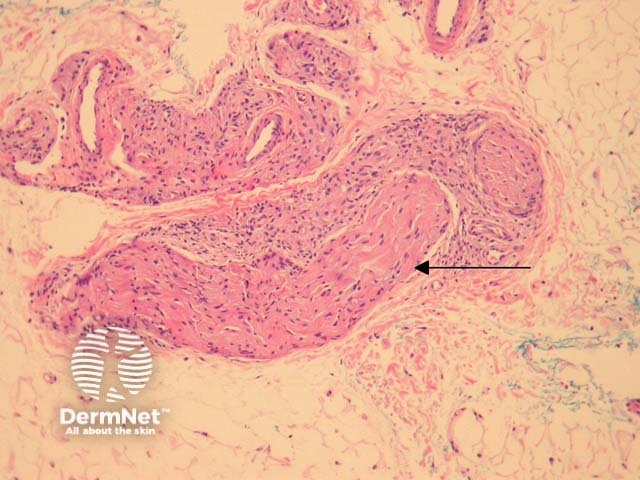

Tuberculoid leprosy – There is a tuberculoid or sarcoidal granulomatous reaction throughout the dermis consisting of some Langhans giant cells, macrophages in tight clusters, and few accompanying lymphocytes (figure 3). The infiltrate may extensively infiltrate peripheral nerves (figure 4, arrow), vessels, the overlying epidermis and arrectores pilorum.

Figure 4